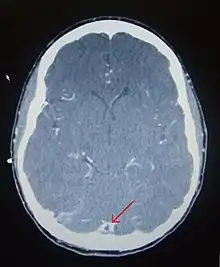

There are various neuroimaging investigations that may detect cerebral sinus thrombosis. Cerebral edema and venous infarction may be apparent on any modality, but for the detection of the thrombus itself, the most commonly used tests are computed tomography (CT) and magnetic resonance imaging (MRI), both using various types of radiocontrast to perform a venogram and visualise the veins around the brain.[4]

Computed tomography, with radiocontrast in the venous phase (CT venography or CTV), has a detection rate that in some regards exceeds that of MRI. The test involves injection into a vein (usually in the arm) of a radioopaque substance, and time is allowed for the bloodstream to carry it to the cerebral veins - at which point the scan is performed. It has a sensitivity of 75-100% (it detects 75-100% of all clots present), and a specificity of 81-100% (it would be incorrectly positive in 0-19%). In the first two weeks, the "empty delta sign" may be observed (in later stages, this sign may disappear).[11]

Magnetic resonance venography employs the same principles, but uses MRI as a scanning modality. MRI has the advantage of being better at detecting damage to the brain itself as a result of the increased pressure on the obstructed veins, but it is not readily available in many hospitals and the interpretation may be difficult.[11]